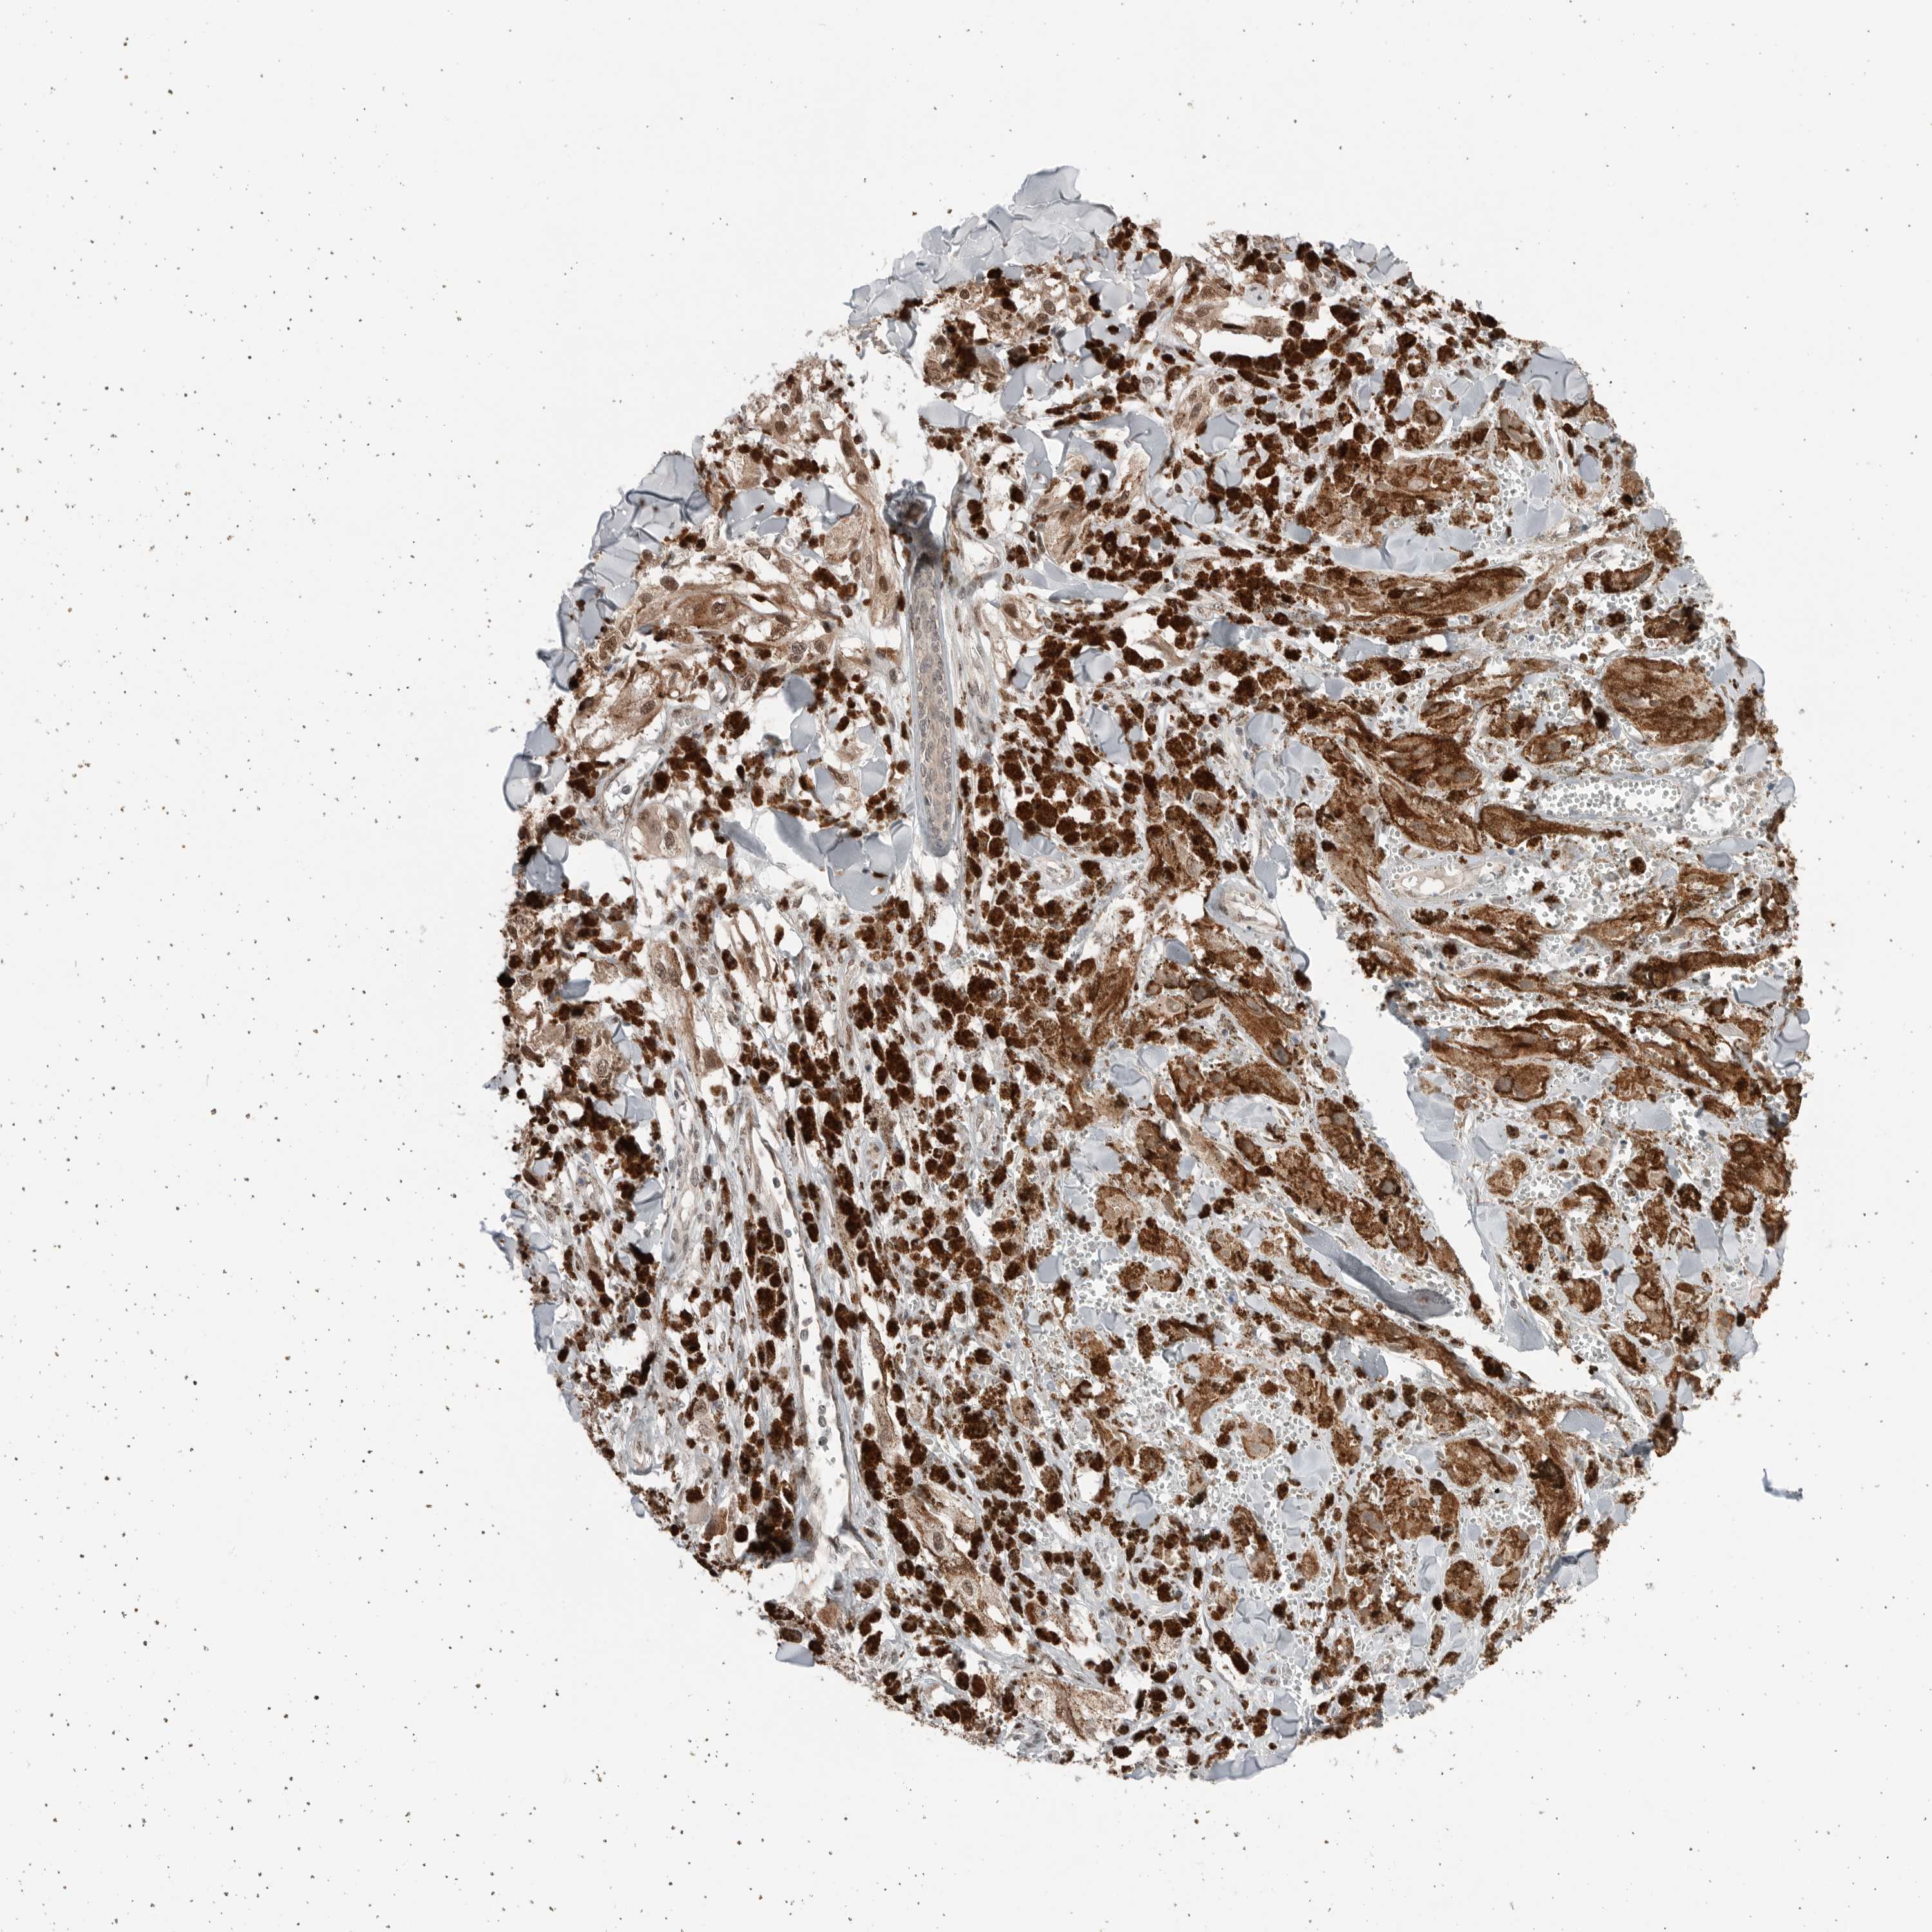

MELANOMA - Protein expressioni

A mouse-over function shows sample information and annotation data. Click on an image to view it in a full screen mode. Samples can be filtered based on level of antibody staining by selecting one or several of the following categories: high, medium, low and not detected. The assay and annotation is described here.

Note that samples used for immunohistochemistry by the Human Protein Atlas do not correspond to samples in the TCGA dataset.

Antibody stainingi

Antibody staining in the annotated cell types in the current human tissue is reported as not detected, low, medium, or high, based on conventional immunohistochemistry profiling in selected tissues. This score is based on the combination of the staining intensity and fraction of stained cells.

Each image is clickable and will lead to virtual microscopy that enables deeper exploration of all samples and also displays staining intensity scores, fraction scores and subcellular localization as well as patient and tissue information for each sample.

Antibody HPA024823

Staining

High

Medium

Low

Not detected

Intensity

Strong

Moderate

Weak

Negative

Quantity

>75%

75%-25%

<25%

None

Location

Nuclear

Cytoplasmic/membranous

Cytoplasmic/membranous,nuclear

Malignant melanoma, NOS

Malignant melanoma, Metastatic site